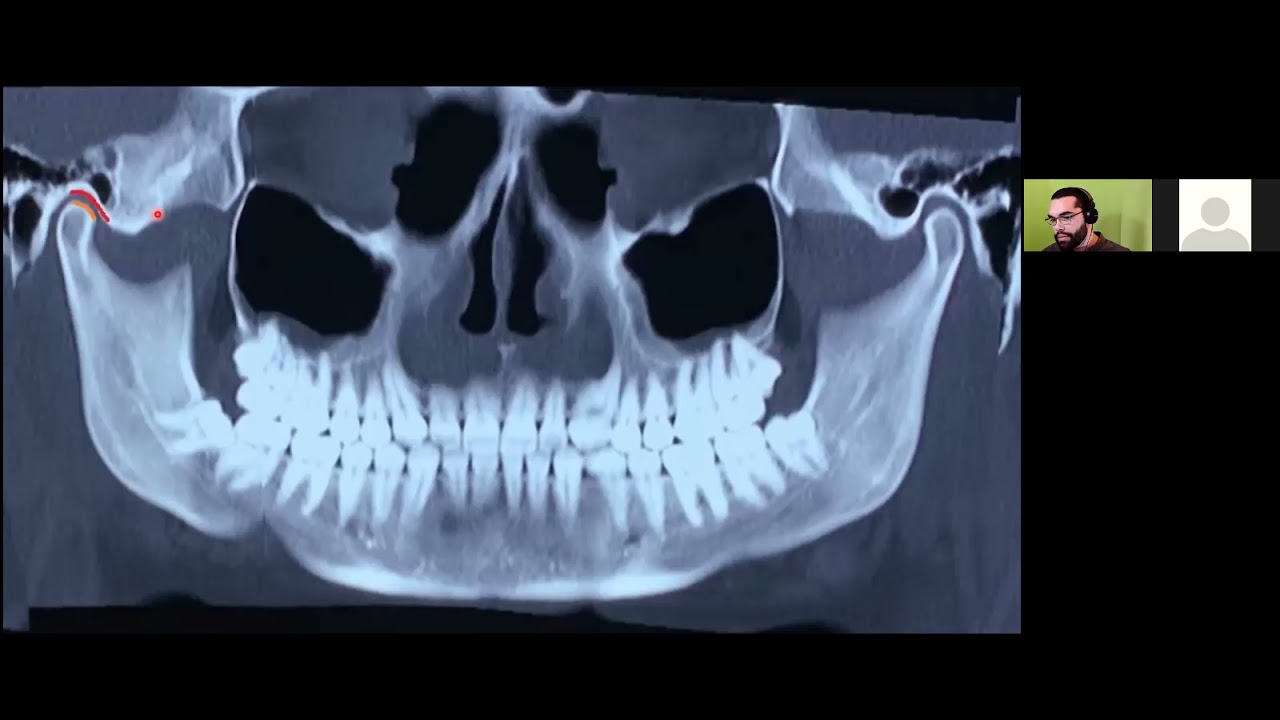

- Radiologia e diagnóstico por imagem odontológico

- Radiologia odontológica

- Avaliação de radiografia

- Disfunção da ATM

Raphael foi extremamente atencioso durante toda a primeira consulta realizada. Demonstrou domínio técnico e teórico da sua área de atuação e fez uma análise completa da minha boca, através da radiografia apresentada. Profissionais dedicados e competentes assim é que levam nosso país pra frente!